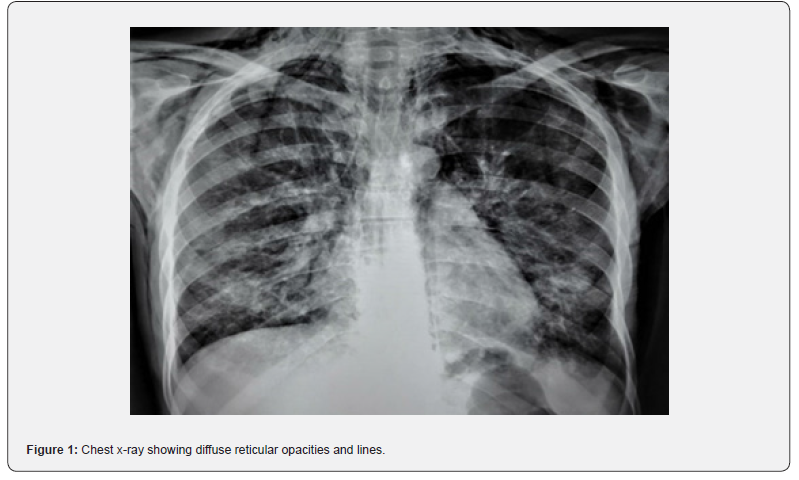

A 30-year-old man was admitted to the emergency room for stage 3 dyspnoea of the MRC classification, with signs of chest muscle tightness, fever at 39° and sweating. After conditioning and stabilizing the patient on the ventilatory level, the physical examination showed crackles on pulmonary auscultation, heart sounds were well perceived, there was no abnormality in the rest of the ‘physical examination. Oxygen saturation was low at 89% in room air. Blood pressure was 110/08mmHg. Chest x-ray showed diffuse nodular opacities in both lung fields as well as reticular lines (Figure 1). Chest CT showed left basal consolidation and scattered ground glass hyper densities in both lungs (Figure 2A and 2B). The biological assessment showed white blood cells at 13,000 e/mm3, a CRP at 100mg/l. A rapid test for positive HIV infection that has been confirmed by serology after patient consent. Normal liver and kidney function.

In our case, the pneumomediastinum occurred because of an alveolar breach caused by an alveolar cyst secondary to pneumocystosis. The clinical presentation of pneumomediastinum is generally manifested by sudden retrosternal pain, cough or neck pain [12]. Dyspnea, dysphagia or fever are elements that point to the rupture of the aero-digestive tract or mediastinitis, which is a therapeutic emergency. In our case dyspnea, fever and hypoxia were at the forefront. The clinical examination highlights in the majority of cases a subcutaneous emphysema which results in a swelling of the thorax or the neck, and by a sound of crepitation on palpation of the skin. The chest X-ray shows fine linear clarity, air sometimes delimits the aortic button and the ascending aorta [13-14], the sign of the continuous diaphragm or the flying thymus in children is not constant. In the profile shot, the air is in the form of a retro-sternal clarity. The chest x-ray may also show signs of subcutaneous emphysema or pneumothorax. However, 30% of pneumomediastinum are not recognized on chest radiography [15].